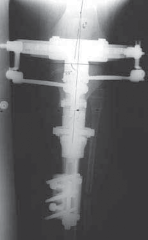

--- TECH FIG 4 • A. The lengthening device is applied. B. A sterile dressing is applied. C,D. Radiographs are taken to verify that there is distraction at the osteotomy site prior to correcting angulation. E,F. Correction is performed until the angulation has been recitified.TECHNIQUES 1 degree of angular deformity and can comfortably be performed four times a day for a correction of about 4 degrees per day until the deformity is corrected (

TECH FIG 4E,F

).

1. Long radiographs are then taken to assess the correction.

2. Secondary deformity (flexion or extension) can be corrected through the secondary hinges, translation screws (one 360-degree turn translates 1 mm), lengthening screws, and the rotation arc (one 90-degree turn corrects 1 degree of rotation).

17. Once the deformity is corrected, all screws and locks on the MAC device are secured. The device can be safely removed after passage of at least 1 month per centimeter of lengthening and a minimum of about 3 months.

1. Radiographs should also demonstrate healing of at least three cortices on each of the AP and lateral views before removal of the fixator.